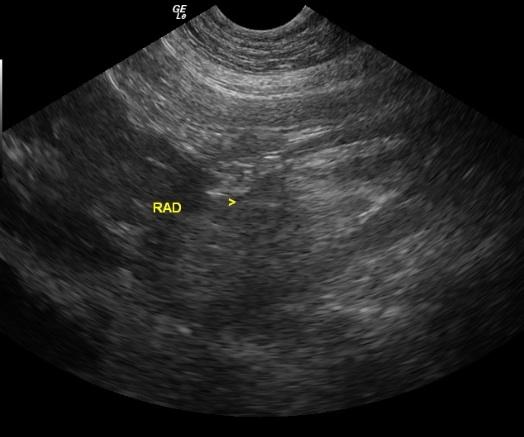

An 8-year-old FS Basset Hound dog was presented for crying throughout the night and vomiting food, fluid, and mucous. On physical examination, she was found to have pink mucous membranes and a normal body temperature. She had bilateral conjunctivitis as well as a bilateral otitis externa (Malassezia). No abnormalities were noted on auscultation of her heart and lungs. The patient was treated symptomatically as an outpatient with anti-emetics and gastroprotectants. Six days later, the dog returned as she was depressed and lethargic. She was in lateral recumbency upon presentation and she was hypothermic with pale pink, tacky and cold mucous membranes. She was admitted to the hospital for I.V. fluid therapy and blood work. The serum biochemical profile revealed elevated ALT, elevated AST, and elevated GGT, azotemia, hyperproteinemia, hyperalbuminemia, hyperglobulinemia, hyperbilirubinemia, hyperkalemia, hypercalcemia, hyperphosphatemia, hypermagnesemia, hyperamylasemia, and an elevated CK. The CBC showed an elevated hemoglobin and leukocytosis consisting of a monocytosis and eosinophilia.